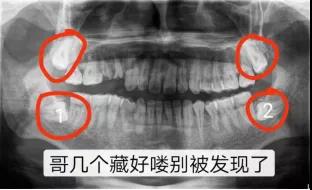

近中阻生智齿,也就是图中1、2两颗横着向牙列方向长的智齿,非常容易将邻近的牙“顶坏”,所以不得不将这两颗牙拔掉。像智齿这样的下颌槽牙的牙根离面部神经非常近,一不小心就可能伤到神经,导致面部没有知觉。而牙片可以清晰地看到牙根与神经的距离,确定拔牙是不是有风险,这也是为什么拔牙都要拍牙片的原因。这口牙只能用“出车祸”来形容了。本以为下颌大牙先天性缺失,不曾想是牙胚的生长方向错了,大牙长不出来。

以上仅仅是列举了茫茫牙片中几个微不足道的例子,但足以说明牙片的重要性。隐藏在牙龈下方的疾病,医生光凭肉眼是无法看到的,不对症,如何用药?即使是拔除一颗坏牙,也要确定会不会伤害到下颌面部神经。由此可见,牙片是牙医的“第三只眼睛”,能看见肉眼看不到的病灶。